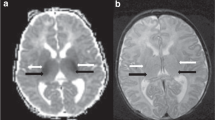

Brain damage measurement, sensorimotor function in the neonatal period, learning and memory ability in adulthood were carried out in mice treated with vitamin C daily for 7 consecutive days following HI brain injury at postnatal day 7.

Vitamin C treatment significantly reduced the hippocampus damage area, infarction volume, hippocampal neuron loss, and suppressed the neuroinflammation after HI injury. Additionally, it improved performance on neonatal sensorimotor function tests and learning and memory ability in adulthood.